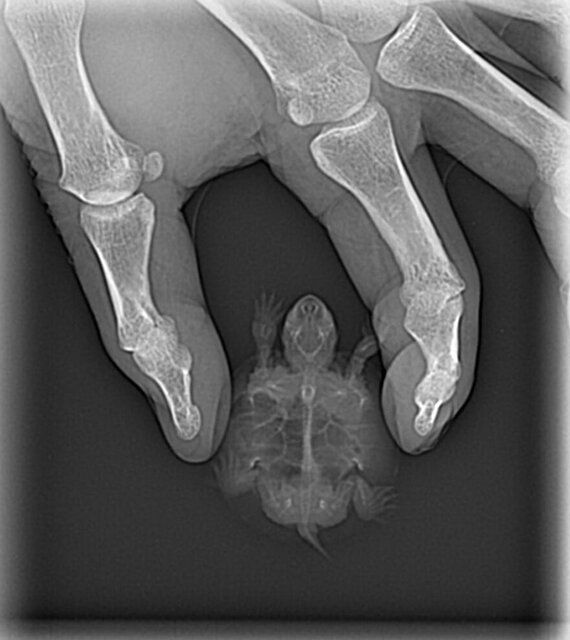

8. Возраст 4-5 мес. Панцирь - 5 см., вес - 14.7 гр. Плохо стала есть, пропускала прием пищи, открывала рот, издавала звуки, появился крен на правую сторону. 10 дней назад

9. В ветклинику "9 жизний" обращались 7 дней назад. Доктор Сыбатуллов Сергей Семигуллович. Препараты не вводились. Врач поставил диагноз - пневмония, по рентген снимкам и рекомендовал: Энромаг 5% 1 мл развести в 250 мл воды ( 28 град), 1 раз в сутки 5-10 дней делать ванночки по  15 мин,  1 раз в 24 часа 2 дня, остальные 1 раз в 48 часов. Крепкий отвар ромашки, календула - купать 2 раза в сутки по 15 мин. при 28 градусах воды 10 дней.

Доброго времени суток. Нам прислали снимки. Посмотрите . И просчитайте пжл дозировку уколов. Возможности онлайн-консультации на данный момент нет.

9b91aa00b174916.jpg

9e444be3b204376.jpg

e4b8d160f9593b2.jpg